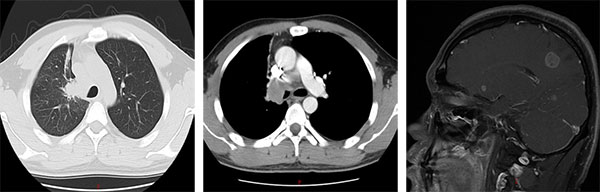

“刚开始服药时,心里总有些忐忑,怕效果不如预期。”服药第3天,咳嗽症状明显减轻;8周后复查,胸部CT显示肺部病灶显著缩小,阻塞支气管的肿瘤组织基本消失;70天,头颅核磁也提示脑转移灶体积缩小、部分微小病灶完全消失。小申的抗癌小本本上记录着他每一天的状况改善。就这样,在治疗的第三个月,小申就重新回到了工作岗位,气色越来越好,变得和常人无异。

治疗后(2025年06月)

从2016年12月到2025年9月,小申坚持靶向治疗已逾8年,无进展生存期(PFS)达105个月。治疗初期,他最大的愿望只是“活过3年,能看到孩子上小学”,如今孩子早已入学,他不仅从未因病情中断美发工作,2020年疫情期间还主动加入社区志愿服务,为居家隔离居民提供生活帮助。